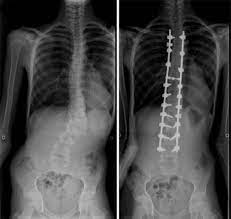

Twenty Five Year Old Man Affected By Marfan Syndrome With Scoliosis Download Scientific Diagram

Surgical Treatment Of Spinal Deformities In Marfan Syndrome Long Term Follow Up Results Using Different Instrumentations Palmisani M Dema E Rava A Palmisani R Girardo M Cervellati S J Craniovert Jun Spine